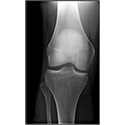

Interactive Radiology